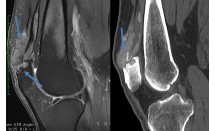

Luxation rétrolunaire pure du carpe

La luxation périlunaire du carpe est la luxation intracarpienne la plus fréquente dans laquelle le lunatum est le pivot. C'est une pathologie rare et grave du sujet jeune. La forme typique, mais pas la plus fréquente, est la luxation rétrolunaire pure (LRP) du carpe.